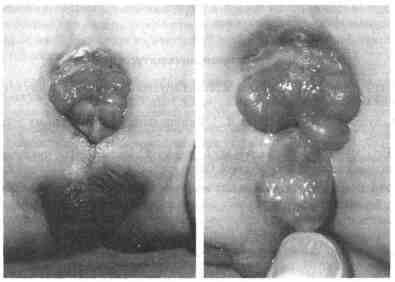

Новорожденный с экстрофией мочевого пузыря 5. Типичны ли изменения верхних мочевыводящих путей у новорожденных пациентов с экстрофией мочевого пузыря? Нет Однако описаны некоторые аномалии, например подковообразная почка и дис-плазия. Новорожденным необходимо провести ультразвуковое исследование. 1 6. Какие проблемы связаны с открытой слизистой оболочкой мочевого пузыря? Обычно таких проблем немного Основными задачами являются защита слизистой оболочки мочевого пузыря от повреждения и предотвращение отека слизистой оболочки, который может затруднить закрытие мочевого пузыря. С этой целью слизистая оболочка закрывается силастиковым (silastic) или обыкновенным пластырем Следует принять меры для предотвращения раздражающего действия памперсов и скрепки в области пупка. 7. Перечислите три операции, которые выполняют большинству мальчиков с экстрофией мочевого пузыря. 1 Первичное закрытие мочевого пузыря. Эту операцию обычно проводят в первые дни жизни Мочевой пузырь закрывают, однако никаких попыток по уплотнению шейки мочевого пузыря не предпринимают. После этой операции у новорожденных наблюдается полное недержание мочи. Одновременно у большинства пациентов выполняют подвздошную остеотомию для того, чтобы совместить лобковые кости по средней линии. Это позволяет повысить надежность закрытия мочевого пузыря. 2 Операция по поводу эписпадии. Ее обычно выполняют в б-18-месячном возрасте Существует мнение, что создаваемое при этом добавочное пассивное сопротивление способствует увеличению размеров мочевого пузыря, что облегчает выполнение третьей операции. 3. Реконструкция шейки мочевого пузыря. Двухсторонняя реимплантация мочеточников производится одновременно, чтобы исключить пузырно-мочеточниковый рефлюкс и сместить устья мочеточников от каудальной части мочевого пузыря, которая в ходе реконструкции шейки мочевого пузыря подвергается тубуляризации. 8. Насколько успешным является такой подход? Примерно у 70 % пациентов удается добиться приемлемого уровня удержания мочи (они остаются сухими в течение не менее 3,5-4 ч). 9. Если у больных сохраняется недержание мочи, какие другие способы лечения применяют? Наиболее частой причиной неудач является небольшой размер мочевого пузыря. Это можно исправить посредством аугментационной цистопластики. В самом деле, если объем мочевого пузыря составляет менее 70-80 мл к моменту выполнения реконструкции шейки мочевого пузыря, предварительно требуется дополняющая пластика мочевого пузыря. Если постоянное недержание мочи обусловлено низким сопротивлением в области внутреннего отверстия мочеиспускательного канала, применяются инъекции коллагена, ревизия шейки мочевого пузыря или установка искусственного сфинктера. Последняя возможность — постоянное отведение мочи с формированием резервуара — метод, который используется у незначительного числа пациентов. 10. Назовите два акушерских (гинекологических) осложнения, которые развиваются у женщин с экстрофией мочевого пузыря в анамнезе. Пролапс матки и неправильное предлежание плода. 11. Что происходит, если не оперировать новорожденных с экстрофией? Они могут жить долгой и здоровой жизнью, однако оперативное лечение проводится всегда. Постоянное недержание мочи непереносимо физически и психологически. Кроме того, такие пациенты входят в группу риска развития аденокарциномы вследствие хронического воспаления слизистой оболочки мочевого пузыря. Воспаление слизистой оболочки, прилежащей к устьям мочеточников, может привести также к развитию гидроуретеронефроза. 12. Что такое экстрофия клоаки? Это редко встречающийся сложный порок развития, частота выявления которого составляет один случай на 200 000 живых новорожденных. Он является результатом преждевременного разрыва мембраны клоаки перед ее делением на переднюю и заднюю части. Это приводит к тому, что две части экстрофированного мочевого пузыря разделены экстрофированным илеоцекальным сегментом. Избранная литература Adams М. С., Retik А. В. Exstrophy of the bladder. In: Resnick M. I., Kursh E. D. (eds). Current Therapy in Genitourinary Surgery. St. Louis, Mosby, 1992, pp. 272—275. Caldamone A. A. Anomalies of the bladder and cloaca. In: Gillenwater J. Y., Grayhack J. Т., Howards S. S., Duckett J. W. (eds). Adult and Pediatric Urology, 2nd ed. St. Louis, Mosby, 1991, pp. 2023-2053. Connor J. P., Lattimer J. K., Hensle T. W., Burbige K. A. Primary closure of bladder exstrophy: Long-term functional results in 137 patients. J. Pediatr. Surg., 23: 1102-1106, 1988. Gearhart J. P., Canning D. A., Peppas D. S., Jeffs R. D. Techniques to create continence in the failed bladder exstrophy closure patient. J. Urol, 150:441—443,1993. Gearhart J. P., Jeffs R. D. Augmentation cystoplasty in the failed exstrophy reconstruction J. Urol., 139: 790-793,1988. Gearhart J. P., Jeffs R. D. Bladder exstrophy: Increase in capacity following epispadias repair J. Urol., 142:525-526, 1989. Gearhart J P., Jeffs R. D. State-of-the-art reconstructive surgery for bladder exstrophy at the Johns Hopkms Hospital Am J. Dis. Child., 143: 1475-1478, 1989. Lepor H., Jeffs R. D. Primary bladder closure